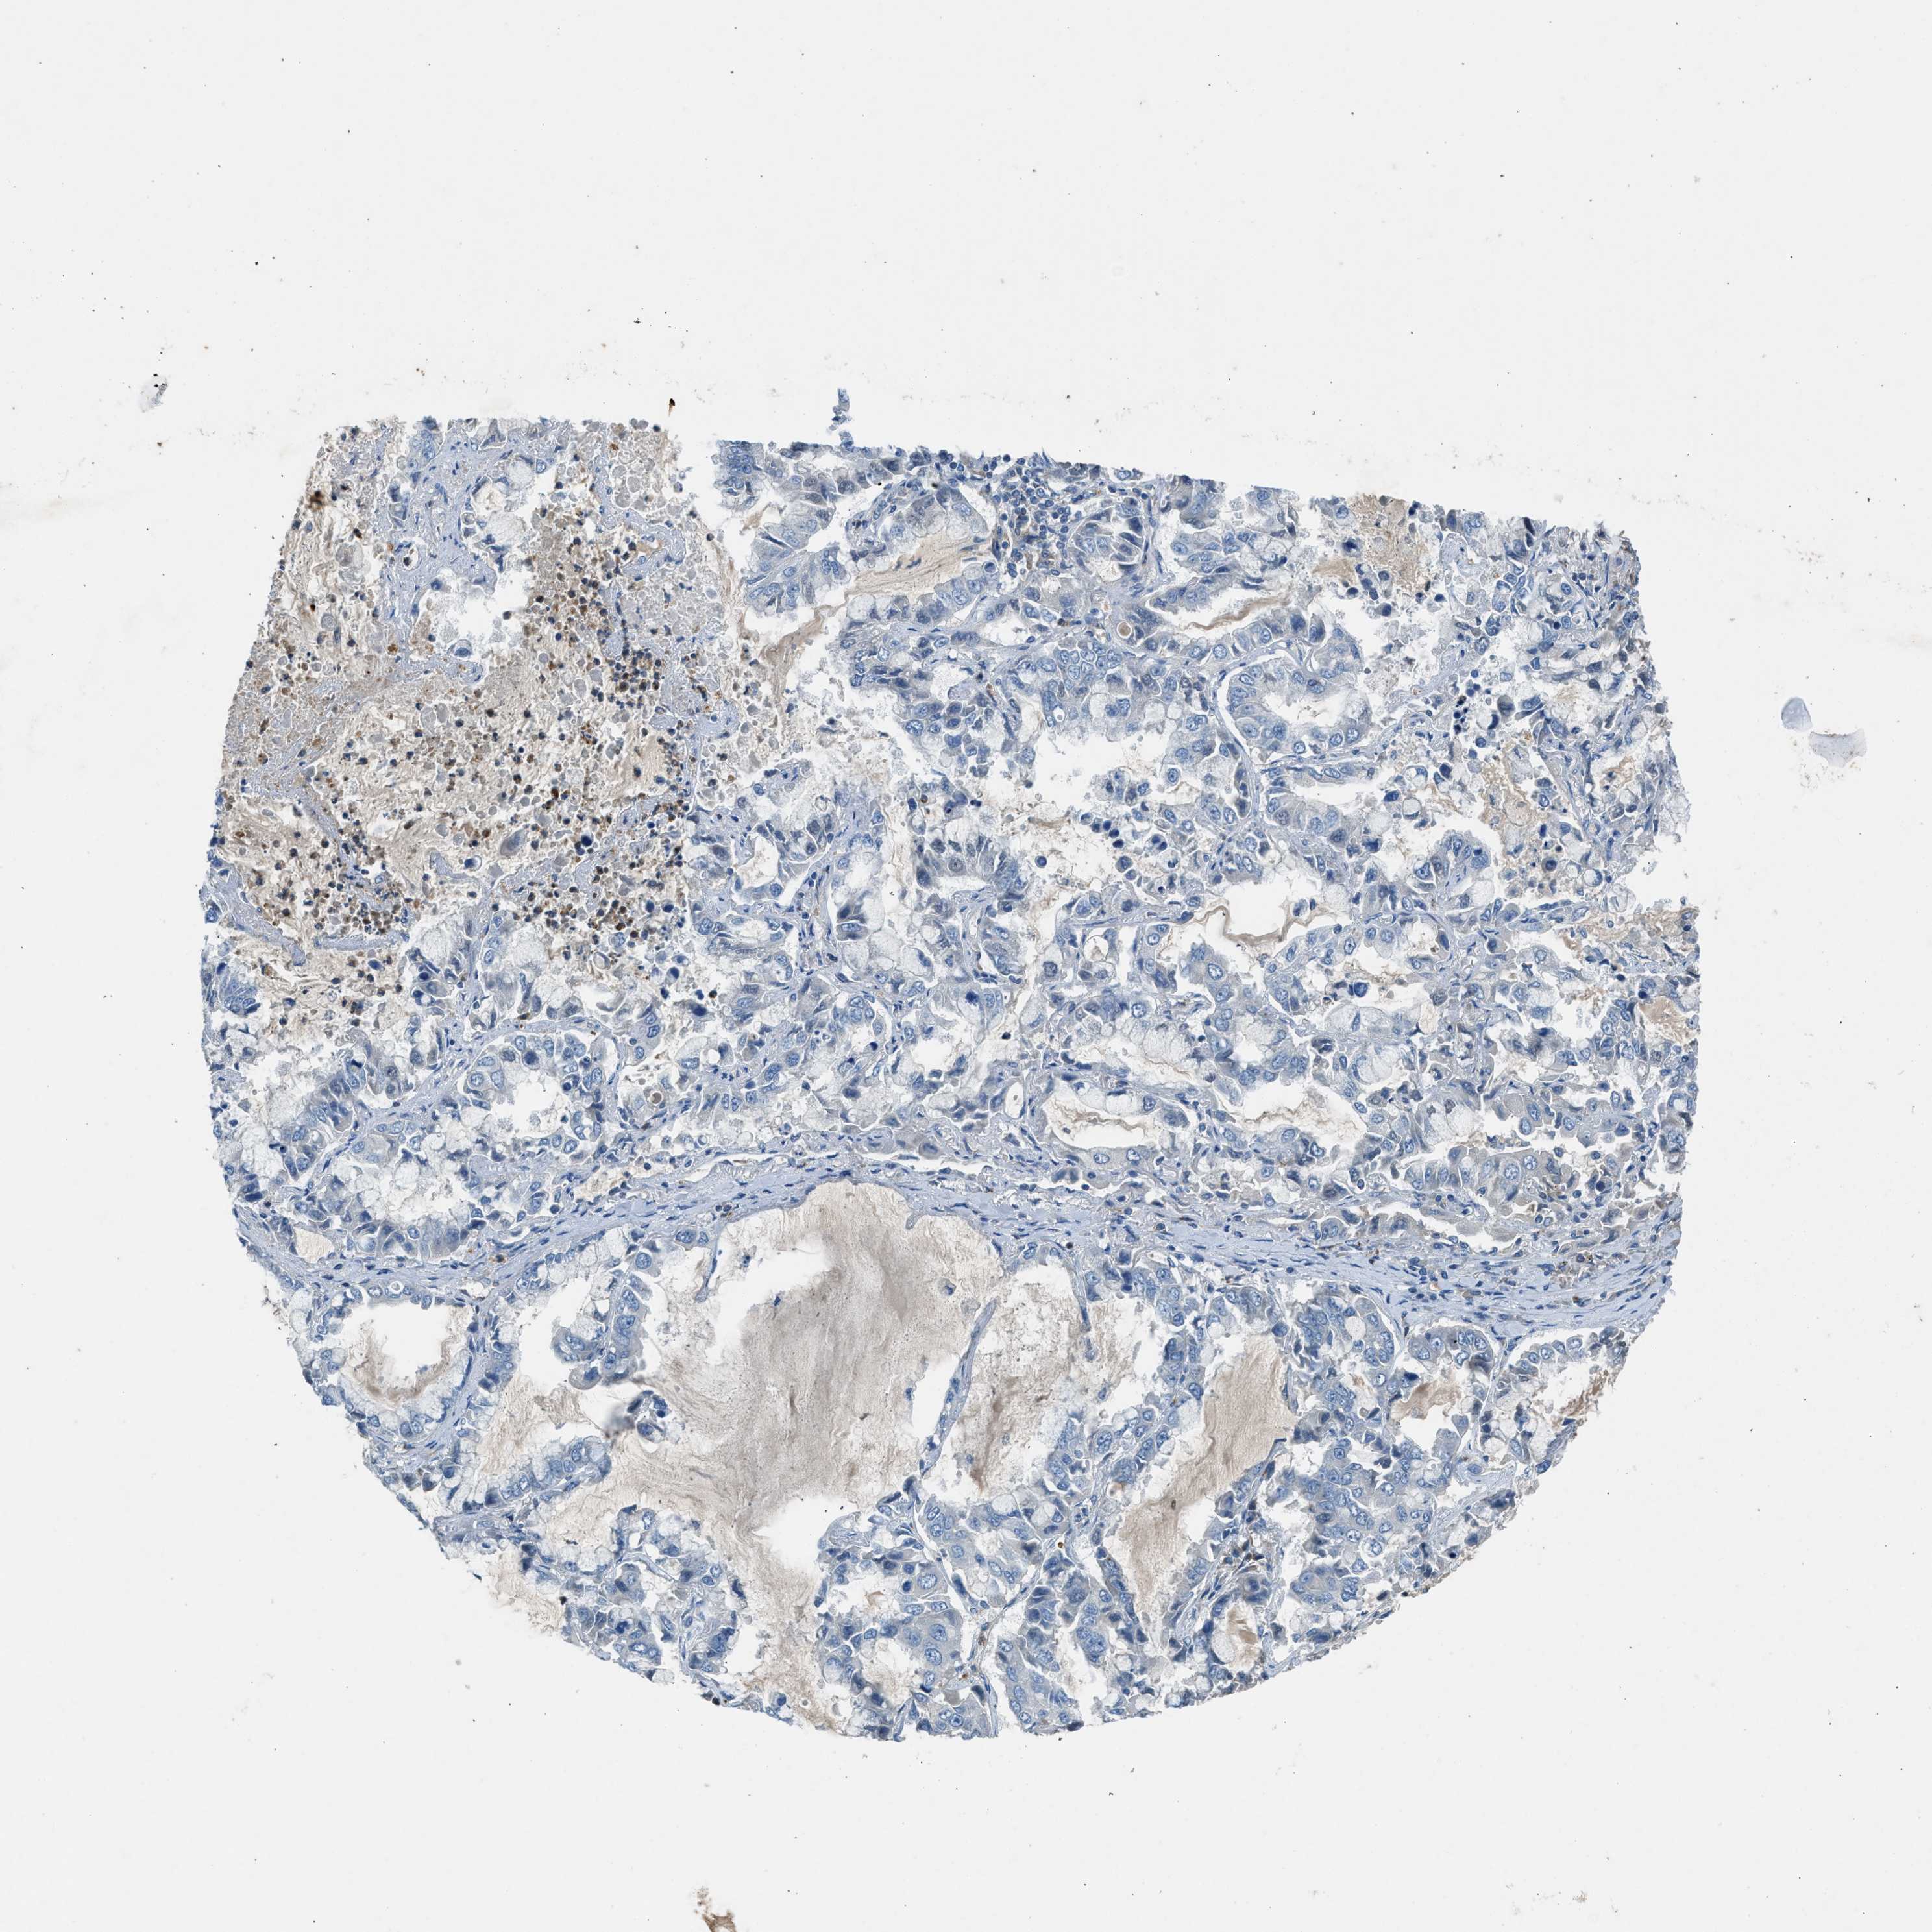

BMP1 is validated prognostic, high expression is unfavorable in Lung Adenocarcinoma (validation)

Best expression cut offi

When clicking on this number, the vertical dashed line indicating cut-off, the interactive survival plot, and the Kaplan-Meier curve will be adjusted to show results based on the best expression cut-off.

: 8.46

Average pTPM 9.7

Number of samples 105